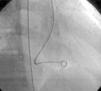

Os motivos de referência mais frequentes foram sopro e/ou cansaço. Todas as fístulas eram de origem congénita. Cinco doentes (42%) tinham patologia cardíaca concomitante: atrésia da pulmonar com septo interventricular intacto (1), canal arterial persistente (1), comunicação interauricular ostium secundum (1), estenose aórtica em válvula aórtica biscúspide (1), estenose pulmonar crítica operada no período neonatal (1). Foram realizadas angiografias selectivas para delinear a anatomia da(s) fístula(s). A embolização foi feita na porção mais distal da fístula, poupando todos os ramos colaterais. Num doente foi realizada uma ansa arteriovenosa através da fístula, com embolização da porção terminal da fístula a partir da aurícula direita. Os doentes foram heparinizados (100 U.I./kg na criança e 5000 U.I. no adulto) e foi feito o controlo posterior através do valor de ACT. Três dos doentes apresentavam duas fístulas e os restantes comunicações fistulosas isoladas. As fístulas eram todas hemodinamicamente significativas e tinham origem no território da coronária direita (n=10), da coronária esquerda (n=3) e da circunflexa (n=2) e drenavam para o ventrículo direito (n=5), artéria pulmonar (n=6), aurícula direita (n=2), seio coronário (n=1) e ventrículo esquerdo (n=1). O material de embolização incluiu 15 coils standard em 3 doentes, 1 coil Jackson® num doente (Figuras 1–3), 27 microcoils em 11 doentes (18 microcoils simples em 7 doentes e 9 microcoils GDC em 4 doentes) e um dispositivo Amplatzer®Duct Occluder num doente (Figuras 4–7). Merece um destaque especial os microcoils GDC, simples ou complexos, que são dispositivos de libertação controlada por electrólise, o que permite que o procedimento seja reversível até à fase final da libertação, após se confirmar a boa posição do dispositivo. Num doente foi testado um plug cardíaco Amplatzer® que não foi libertado por não ser adequado à lesão.

A abordagem clássica da fístula coronária é o encerramento cirúrgico. Em 1997, Mavroudis et al apresentou uma análise sobre resultados cirúrgicos de encerramento de fístulas coronárias em 17 doentes com idades compreendidas entre as seis semanas e os 16,5 anos (idade média 5,5 anos) e tratados entre 1968 e 1996, concluindo que o encerramento cirúrgico de fístulas coronárias foi 100% eficaz e sem mortalidade naquela série, pelo que deve ser o tratamento de eleição nestas situações, devendo o encerramento percutâneo ficar reservado para apenas uma pequena população seleccionada11. Contudo, já em 1991, tinha sido descrito o encerramento percutâneo de sete fístulas coronárias em doentes com idades compreendidas entre os dois e os 67 anos (idade média de 17 anos), que decorreu com sucesso em seis das sete fístulas encerradas e sem complicações durante um tempo de seguimento de quatro meses a quatro anos12. Neste artigo, os autores chamam a atenção para a vantagem do encerramento percutâneo com a possibilidade de se evidenciarem fístulas adicionais após o encerramento da(s) fístula(s) de maiores dimensões apenas visível(is) no encerramento percutâneo. Apesar de tecnicamente mais difícil, fístulas de grandes dimensões a drenarem para a aurícula direita ou para o ventrículo direito podem ser encerradas por via venosa com dispositivos como Amplatzer®Duct Occluder ou plugs, com monitorização do posicionamento adequado do dispositivo através de injecções selectivas retrógradas na artéria coronária, como descrito em 2000 por Pedra et al5 e realizado no nosso caso 9 (Fig. 1 a 4).